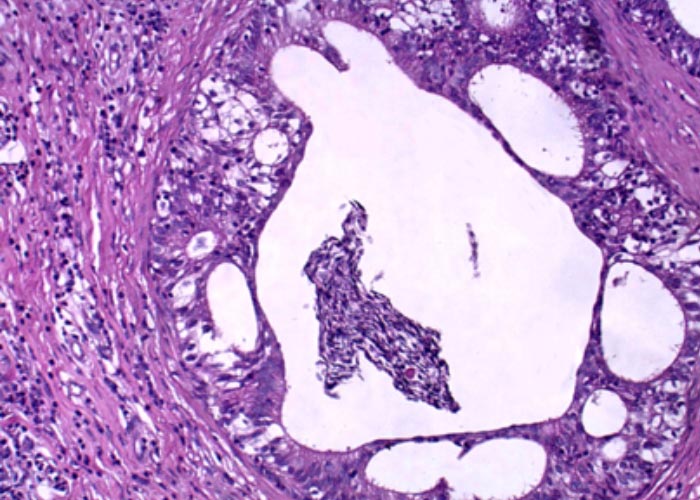

Figure 2 Spermatic granuloma of the tail of the epididymis in a case of Brucella ovis infection (Courtesy of R L Santos Professor, DVM, PhD, Universidade Federal de Minas Gerais, Escola de Veterinária, Departamento de Clínica e Cirurgia Veterinárias, Av. Antonio Carlos 6627, Minas Gerais, 31270-901, Brazil)

Typical lesions in the affected epididymis include solitary or multiple spermatocoeles and spermatic granulomas, which contain a creamy fluid or inspissated, caseous material (Figure 2), thickening due to the presence of a low-grade, non-purulent inflammatory response (Figures 3 and 4), and fibrosis of the interductal connective tissue and the tunica albuginea. In most cases fibrous adhesions form between the tail of the epididymis, the parietal tunica vaginalis and the distal pole of the testis.78